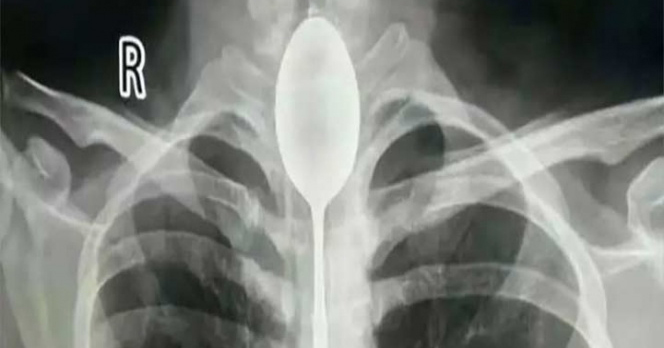

Por apuesta en borrachera chino se traga enorme cuchara

El hecho ocurrió en la ciudad de Urumchi; el joven retado por sus amigos se tragó el cubierto y no logró sacarlo con una cuerda como tenía planeado; un año después acudió al hospital.